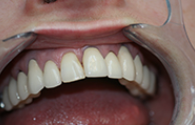

Cas cliniques

Chaque cas est unique nous essayons toujours de privilégier la meilleure solution pour le patient, d'abord d'un point de vue thérapeutique mais aussi d'un point de vue financier.

Ces cas cliniques sont une illustration pédagogique de traitements odontologiques. Leur objectif est de mettre en image des soins dentaires pour une meilleure compréhension de ceux-ci.